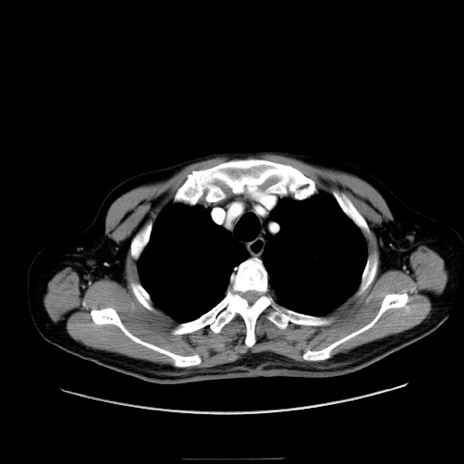

症例30(横断像)

【症例】80歳代男性

【主訴】臍周囲痛

【現病歴】約6時間前から臍下部痛が出現。次第に腹部膨隆・背部痛も生じてきたため来院。背部痛の場所は変化しない。

【身体所見】意識清明、BT 36.3℃、BP  131/87mmHg、P 87bpm、SpO2 100%(RA)、臍周囲自発痛・圧痛あり、反跳痛なし、自発痛部位に一致して板状硬あり、腹部膨隆、腸雑音減弱、CVA tenderness両側陰性。

【データ】WBC 19600、CRP 0.33